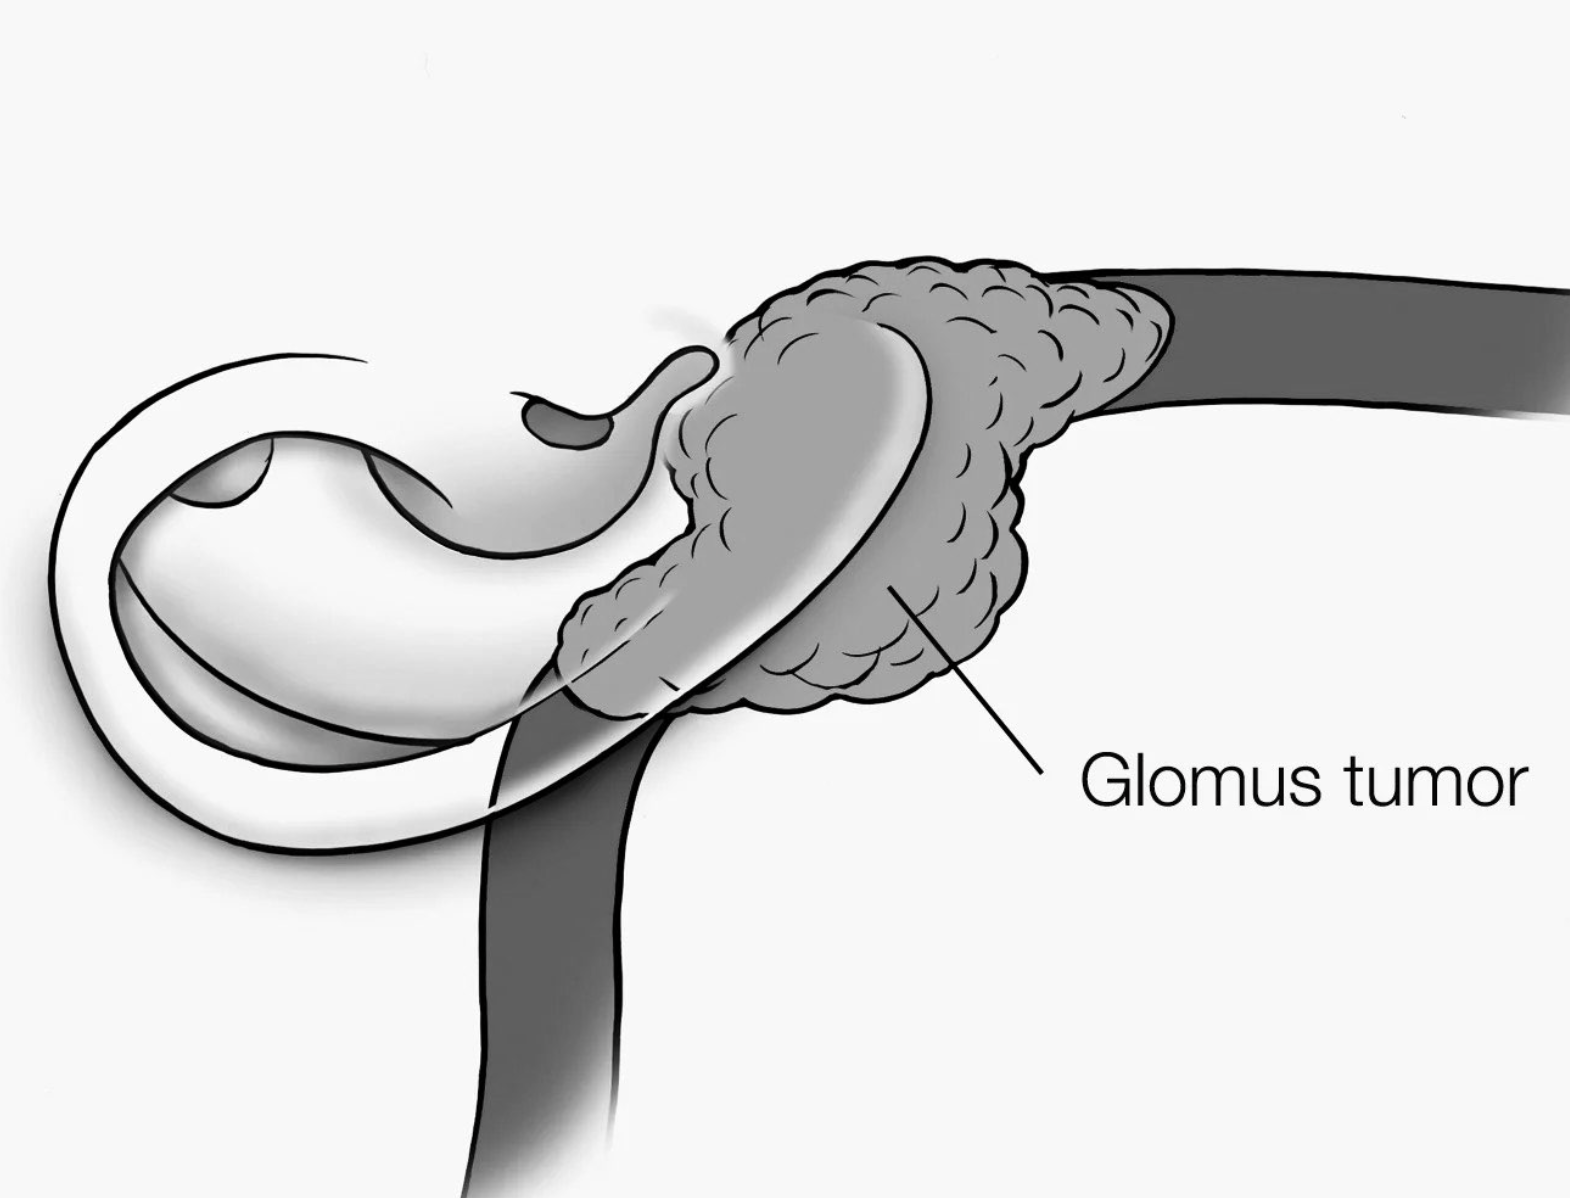

Advanced otology encompasses complex ear and skull base conditions requiring specialized surgical care. We offer cochlear implants and bone conduction implants for hearing loss, treat acoustic neuroma and temporal bone tumors, and perform stapes surgery for otosclerosis. Our team also manages cholesteatoma, superior canal dehiscence, and other advanced ear conditions. Select a topic below to learn more.